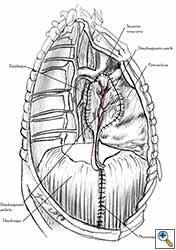

Pericardial reconstruction is indicated after extrapleural pneumonectomy for diffuse malignant pleural mesothelioma. Right-sided pericardioplasty is performed to prevent cardiac dislocation as discussed above. Left sided pericardial defects that result after extrapleural pneumonectomies are large and there is no risk of cardiac strangulation, but reconstruction is recommended in order to prevent constrictive epicarditis (Figure 3) [4].

| Figure 9a: Pericardial defect resulted after right extrapleural pneumonectomy. | Figure 9b: Final aspect of pericardioplasty after right extrapleural pneumonectomy. The mesh is fenestrated. |

Video 1 depicts a pericardial reconstruction with Marlex after a right completion pneumonectomy with pericardiectomy for lung adenocarcinoma (see also Figure 1). The technique of pericardial reconstruction after the resection of invasive mediastinal tumours is illustrated in Figures 8a-c). Video 2 depicts a pericardial reconstruction with Mersilene mesh after the resection of a malignant thymoma invading the anterior pericardium (see also Figure 4b). The technique of right pericardial reconstruction after extrapleural pneumonectomy is illustrated in Figures 9a and 9b). Video 3 depicts a pericardial reconstruction using Gore-Tex Dual Mesh after a left extrapleural pneumonectomy (see also Figure 3). Care must be taken to prevent constriction (Figure 10).

- Left pericardial defects after extrapleural pneumonectomy should be reconstructed.